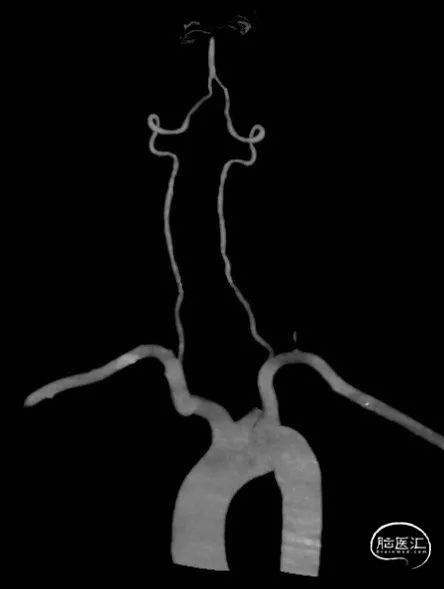

术前CT未见出血,pc-ASPECT 10分。

术前CTA:基底动脉顶端闭塞。